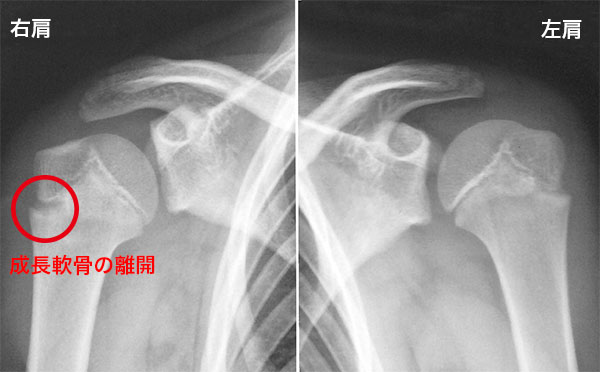

• リトルリーグショルダー(上腕骨骨端線離開)

投球時、投球後、肩をねじるときの痛み

成長期の投球障害で、投球時や投球後に肩の痛みを訴えます。子どもの骨の端の方には骨を形成する細胞が密集する成長線という軟骨(成長軟骨)がありますが、骨に比べて強度が弱く、過度の投球による負荷で損傷し、上腕骨の肩の部分の成長軟骨(骨端線)の離開(骨端線離開)が起こって痛みが表れるスポーツ障害です。放置しておくと痛むだけでなく成長障害にも繋がる可能性もあります。投球動作の他、ラケット競技、あるいは転倒した際に肩から落ちるなどの外傷が、その原因として挙げられます。

投球時に痛み、投球後に痛み、肩をねじると痛みが出ます。

リトルリーグショルダー(上腕骨骨端線離開)のレントゲン